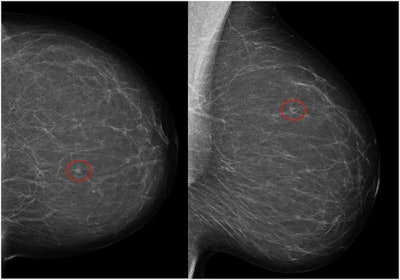

Left craniocaudal and mediolateral oblique mammograms in a 53-year-old woman with an invasive 4-mm histologic grade 1 screen-detected cancer. The exam-level AI score for v1.7 was 5 and 10 for v2.1 (increased AI score). The red circles mark the location of the tumor.Courtesy Marthe Larsen, Prof. Solveig Hofvind et al, European Radiology